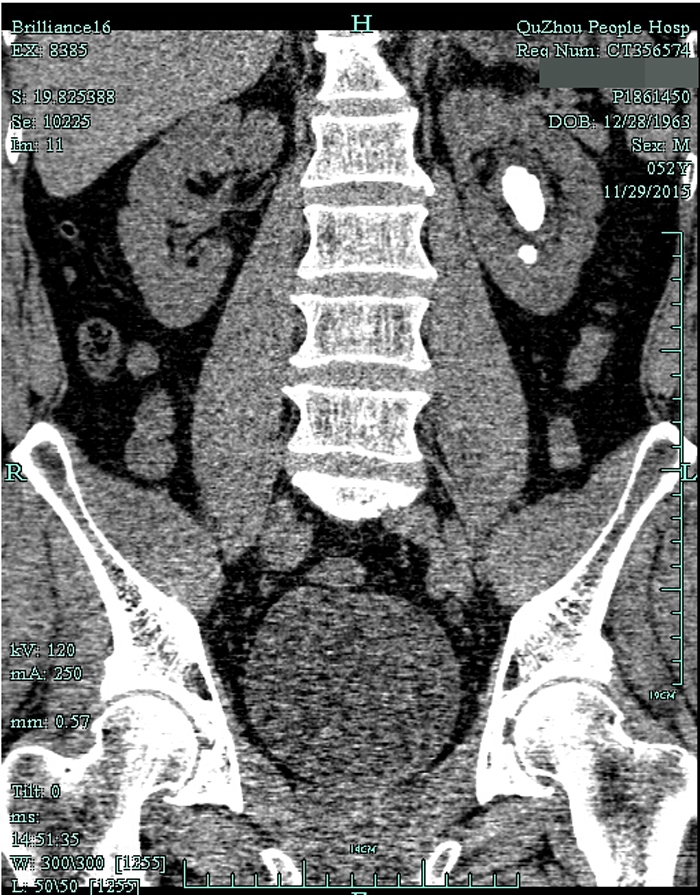

??? 一查泌尿系CT,兄弟倆都是左腎鹿角型結(jié)石,而且已經(jīng)有腎積水。根據(jù)CT檢查結(jié)果以及結(jié)石體積大(3cm)、質(zhì)地硬的特點(diǎn),萬醫(yī)師建議兩人行經(jīng)皮腎鏡碎石取石術(shù),才能將結(jié)石清理干凈。

術(shù)前CT1

術(shù)前CT2